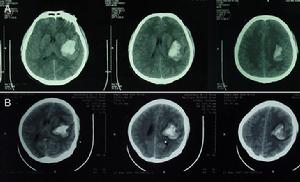

(2)cT掃描不僅可以直接顯示血腫大小和部位,還可以了解腦室受壓和中線結構移位的程度及並存的腦挫裂傷、腦水腫等情況,應及早套用於疑有顱內血腫患者的檢查。硬腦膜外血腫cT表現為顱骨內板與硬腦膜之間的雙凸鏡形或弓形高密度影;急性或亞急性硬腦膜下血腫cT表現為腦表面新月形高密度、混雜密度影,多伴有腦挫裂傷和腦受壓;腦內血腫表現為腦挫裂傷區附近或腦深部白質內類圓形或不規則高密度影。

顱內血腫--CT(1)、手術治療可根據CT所見採用骨瓣或骨窗開顱,清除血腫,妥善止血。血腫清除後,如硬腦膜張力高或疑有硬膜下血腫時,應切開硬膜探查。對少數病情危急,來不及做CT等檢查者,應直接手術鑽孔探查,再擴大成骨窗清除血腫。

(2)、非手術治療凡傷後無明顯意識障礙,病情穩定,cT所示血腫量少於30rnl,中線結構移位小於1.0cm者,可在密切觀察病情的前提下,採用非手術治療。